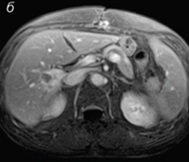

MRI pred terapijo

MRI 30 dni po začetku terapije